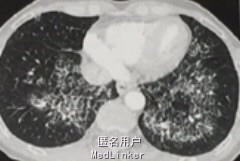

查体示肺部听诊为浊音,CT示双肺弥漫碎石样阴影,沿肺门分布,散在高密度影,与肺泡分布相关。